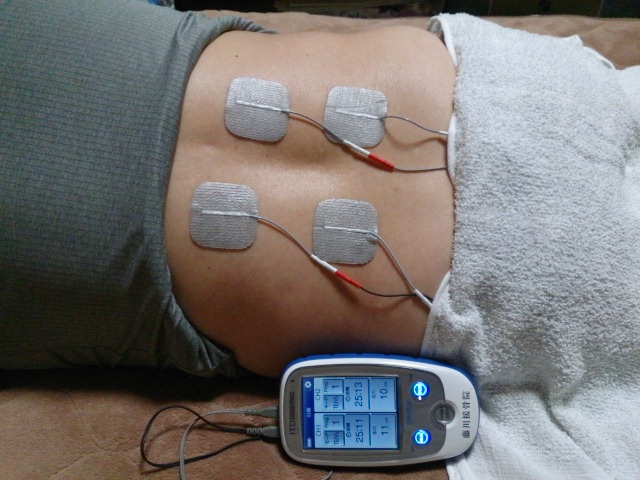

仕事でPCを使う、目が疲れて肩が凝って痛むなどの症状で

仕事でPCを使う、目が疲れて肩が凝って痛むなどの症状で